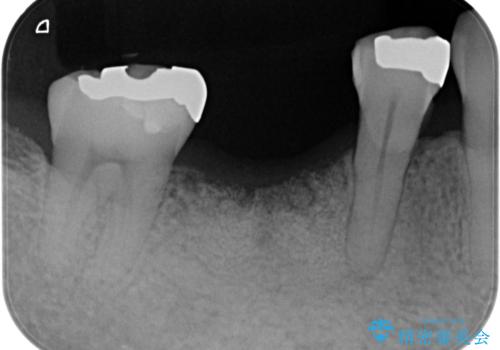

保存できない状態でしたので抜歯をして歯槽堤保存術を行いました。その後大臼歯部にインプラント治療を行いました。

欠損部に1本だけインプラントを埋入しても大きな被せ物になってしまい清掃性が悪くなるので清掃性が良くなるように2本小臼歯用のインプラントを埋入しました。

無事インプラントが入りました。

インプラント治療をしてもメンテナンスを怠っているとインプラント歯周炎になるリスクがあがるのでメンテナンスをお勧めします。